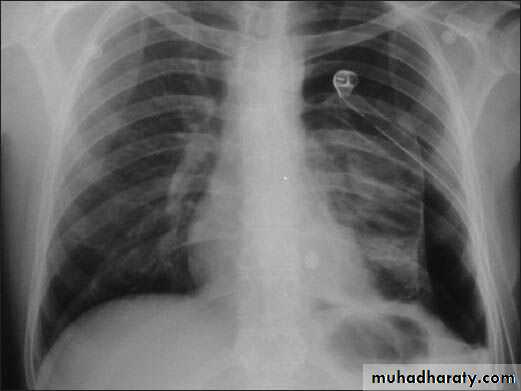

Dilated vein on chest (SVC obstruction)